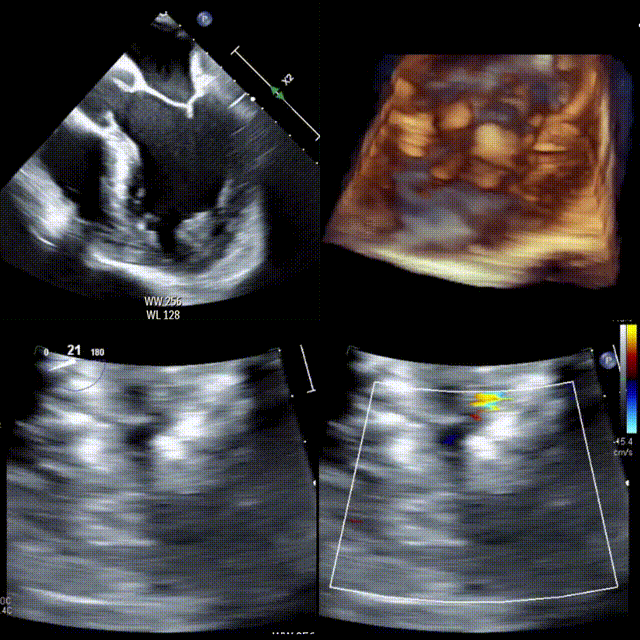

患者否认发热、非法药物使用、恶性肿瘤或全身症状。三维经食管超声心动图(TEE)显示心尖部过度小梁化,隐窝间可见彩色血流(图 B,视频2),超声对比增强未见血栓。

图B 经食管超声心动图(食管中段四腔心切面)显示远场外侧壁小梁化明显